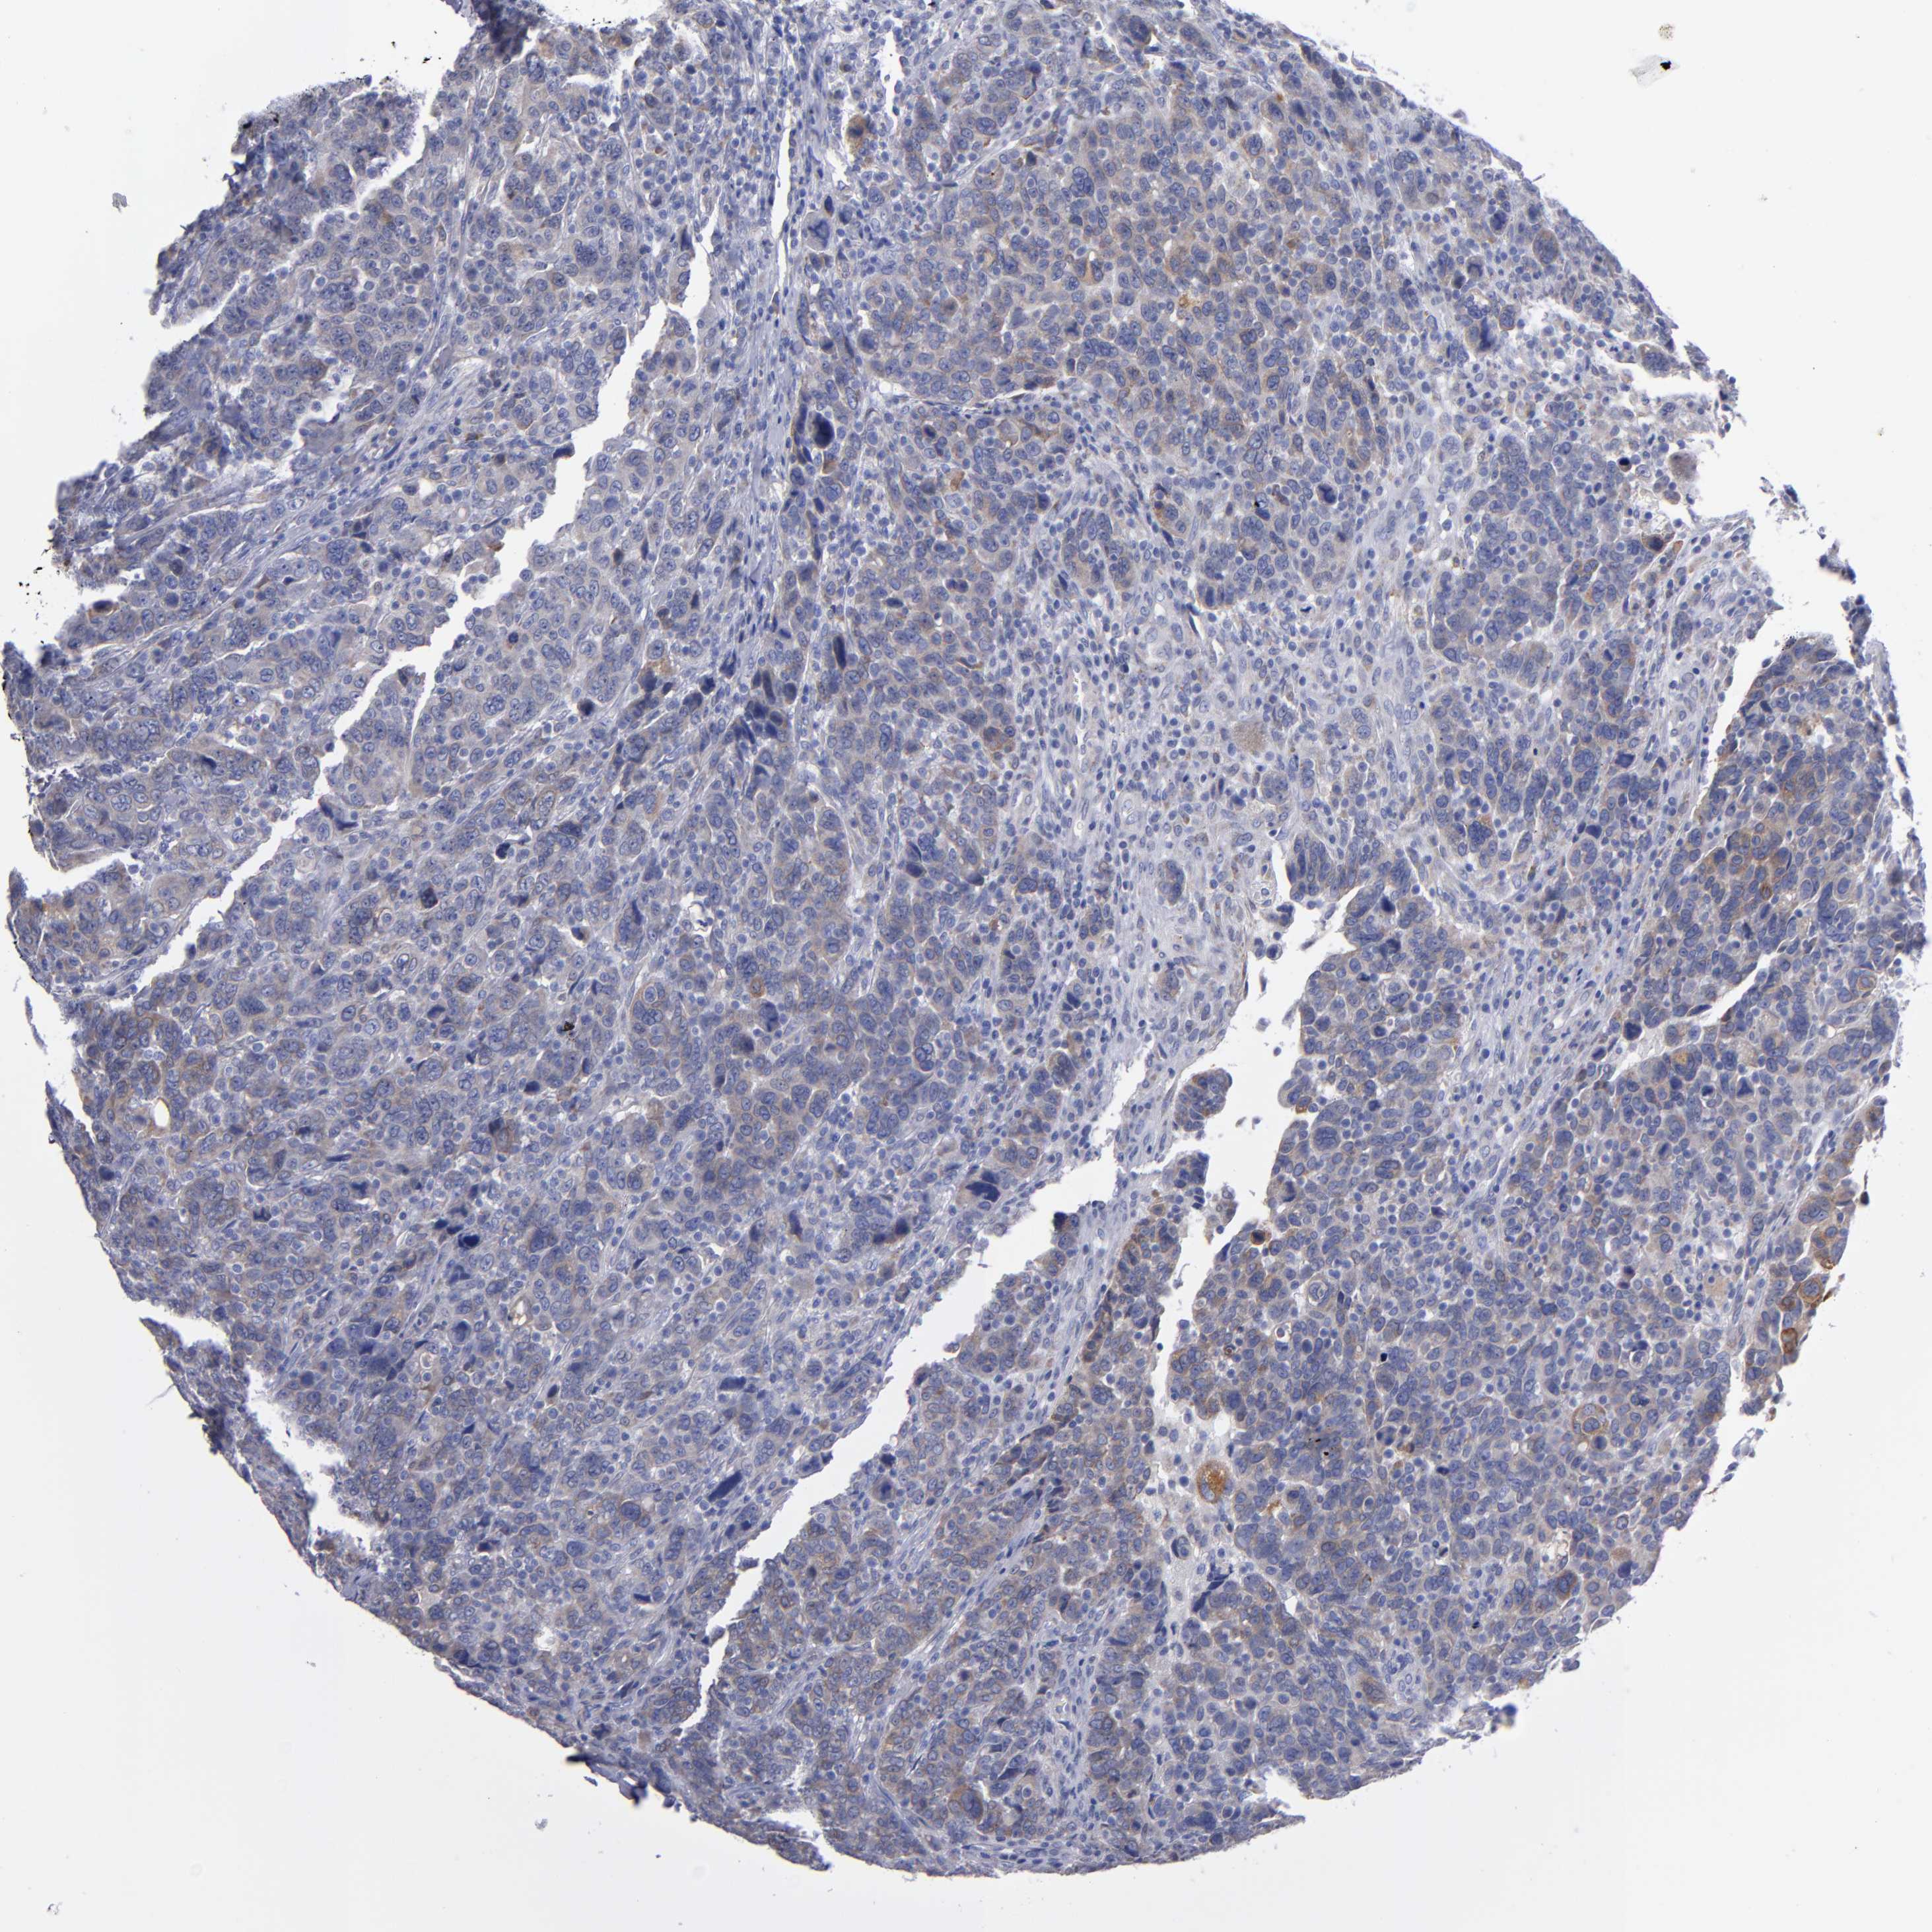

CANCER BREAST CANCER Show tissue menu

BRCA TCGA BRCA VALIDATION PROTEIN EXPRESSION

ANTIBODIES

AND

VALIDATION